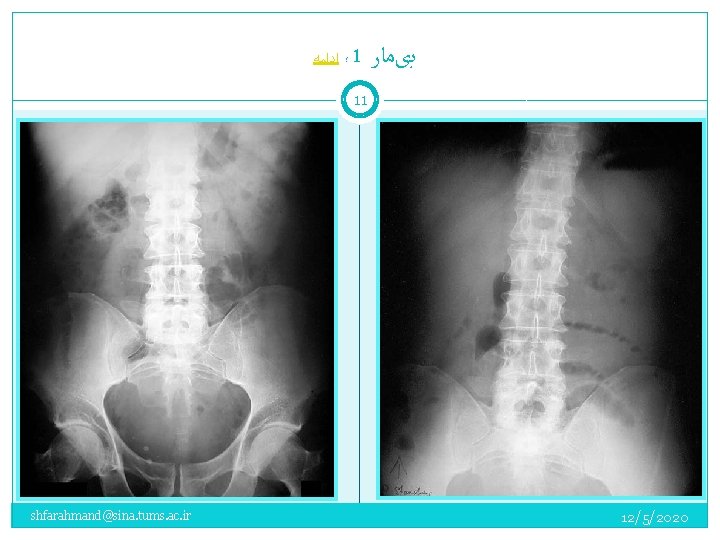

؛ ﺍﺩﺍﻣﻪ 1 ﺑیﻤﺎﺭ 10 A 50 -year-old man complained of periumbilical and left lower quadrant abdominal pain that began earlier in the day. The pain was intermittent, “crampy” in character, and accompanied by anorexia and vomiting. He had a normal bowel movement the previous day. He had not experienced similar pain in the past. There was no history of prior abdominal surgery. On examination: the patient was afebrile and in moderate distress due to his abdominal pain. Bowel sounds were present, and the abdomen was mildly distended with periumbilical tenderness, but no rebound tenderness. shfarahmand@sina. tums. ac. ir 12/5/2020

؛ ﺍﺩﺍﻣﻪ 1 ﺑیﻤﺎﺭ 11 shfarahmand@sina. tums. ac. ir 12/5/2020

1 ﺑیﻤﺎﺭ 14 Left Incarcerated Inguinal H. shfarahmand@sina. tums. ac. ir ﻣﺠﺪﺩﺍ ﺑیﻤﺎﺭ ﺩﻗیﻖ ﻣﻌﺎیﻨﻪ ﺷﺪ 12/5/2020